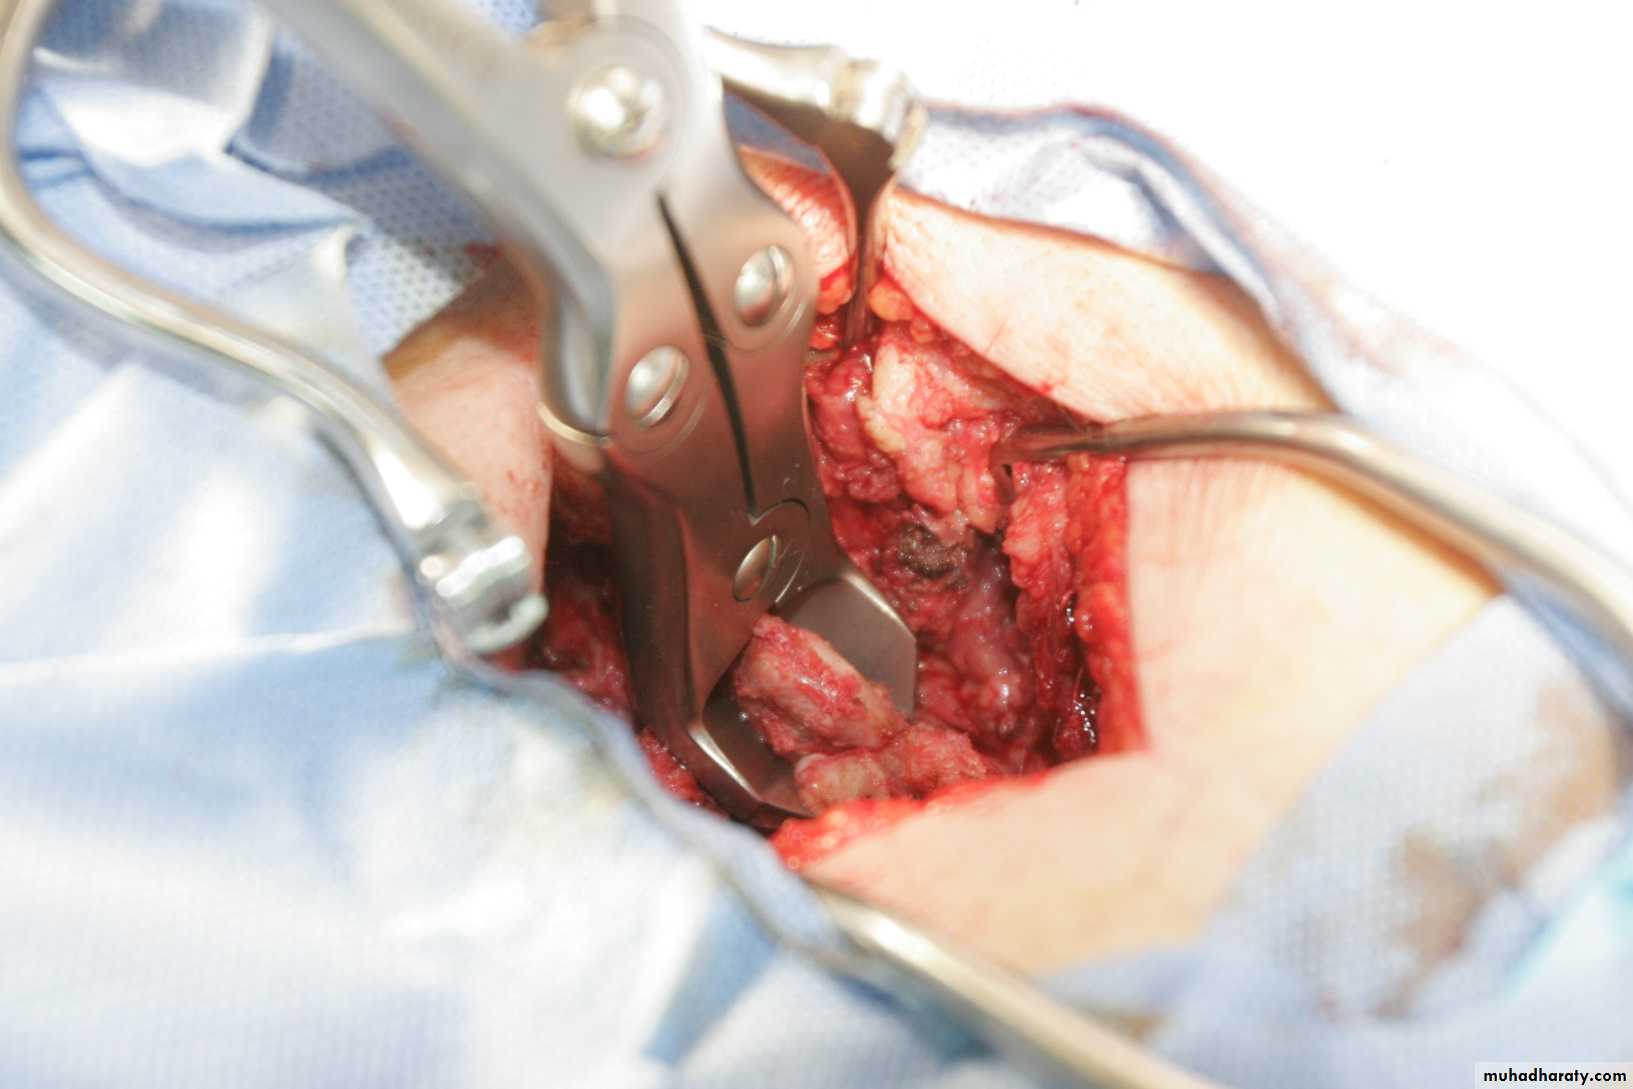

- open laminectomy with discectomy

- micro discectomy

Surgery